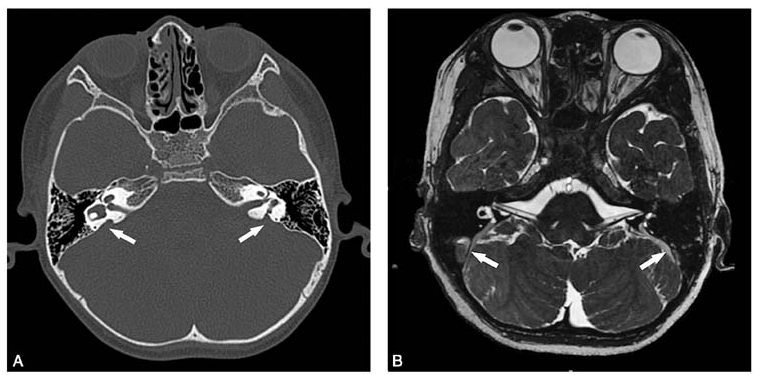

颞骨高分辨率ct示双侧前庭导水管扩大并与前庭池相通(图1a).